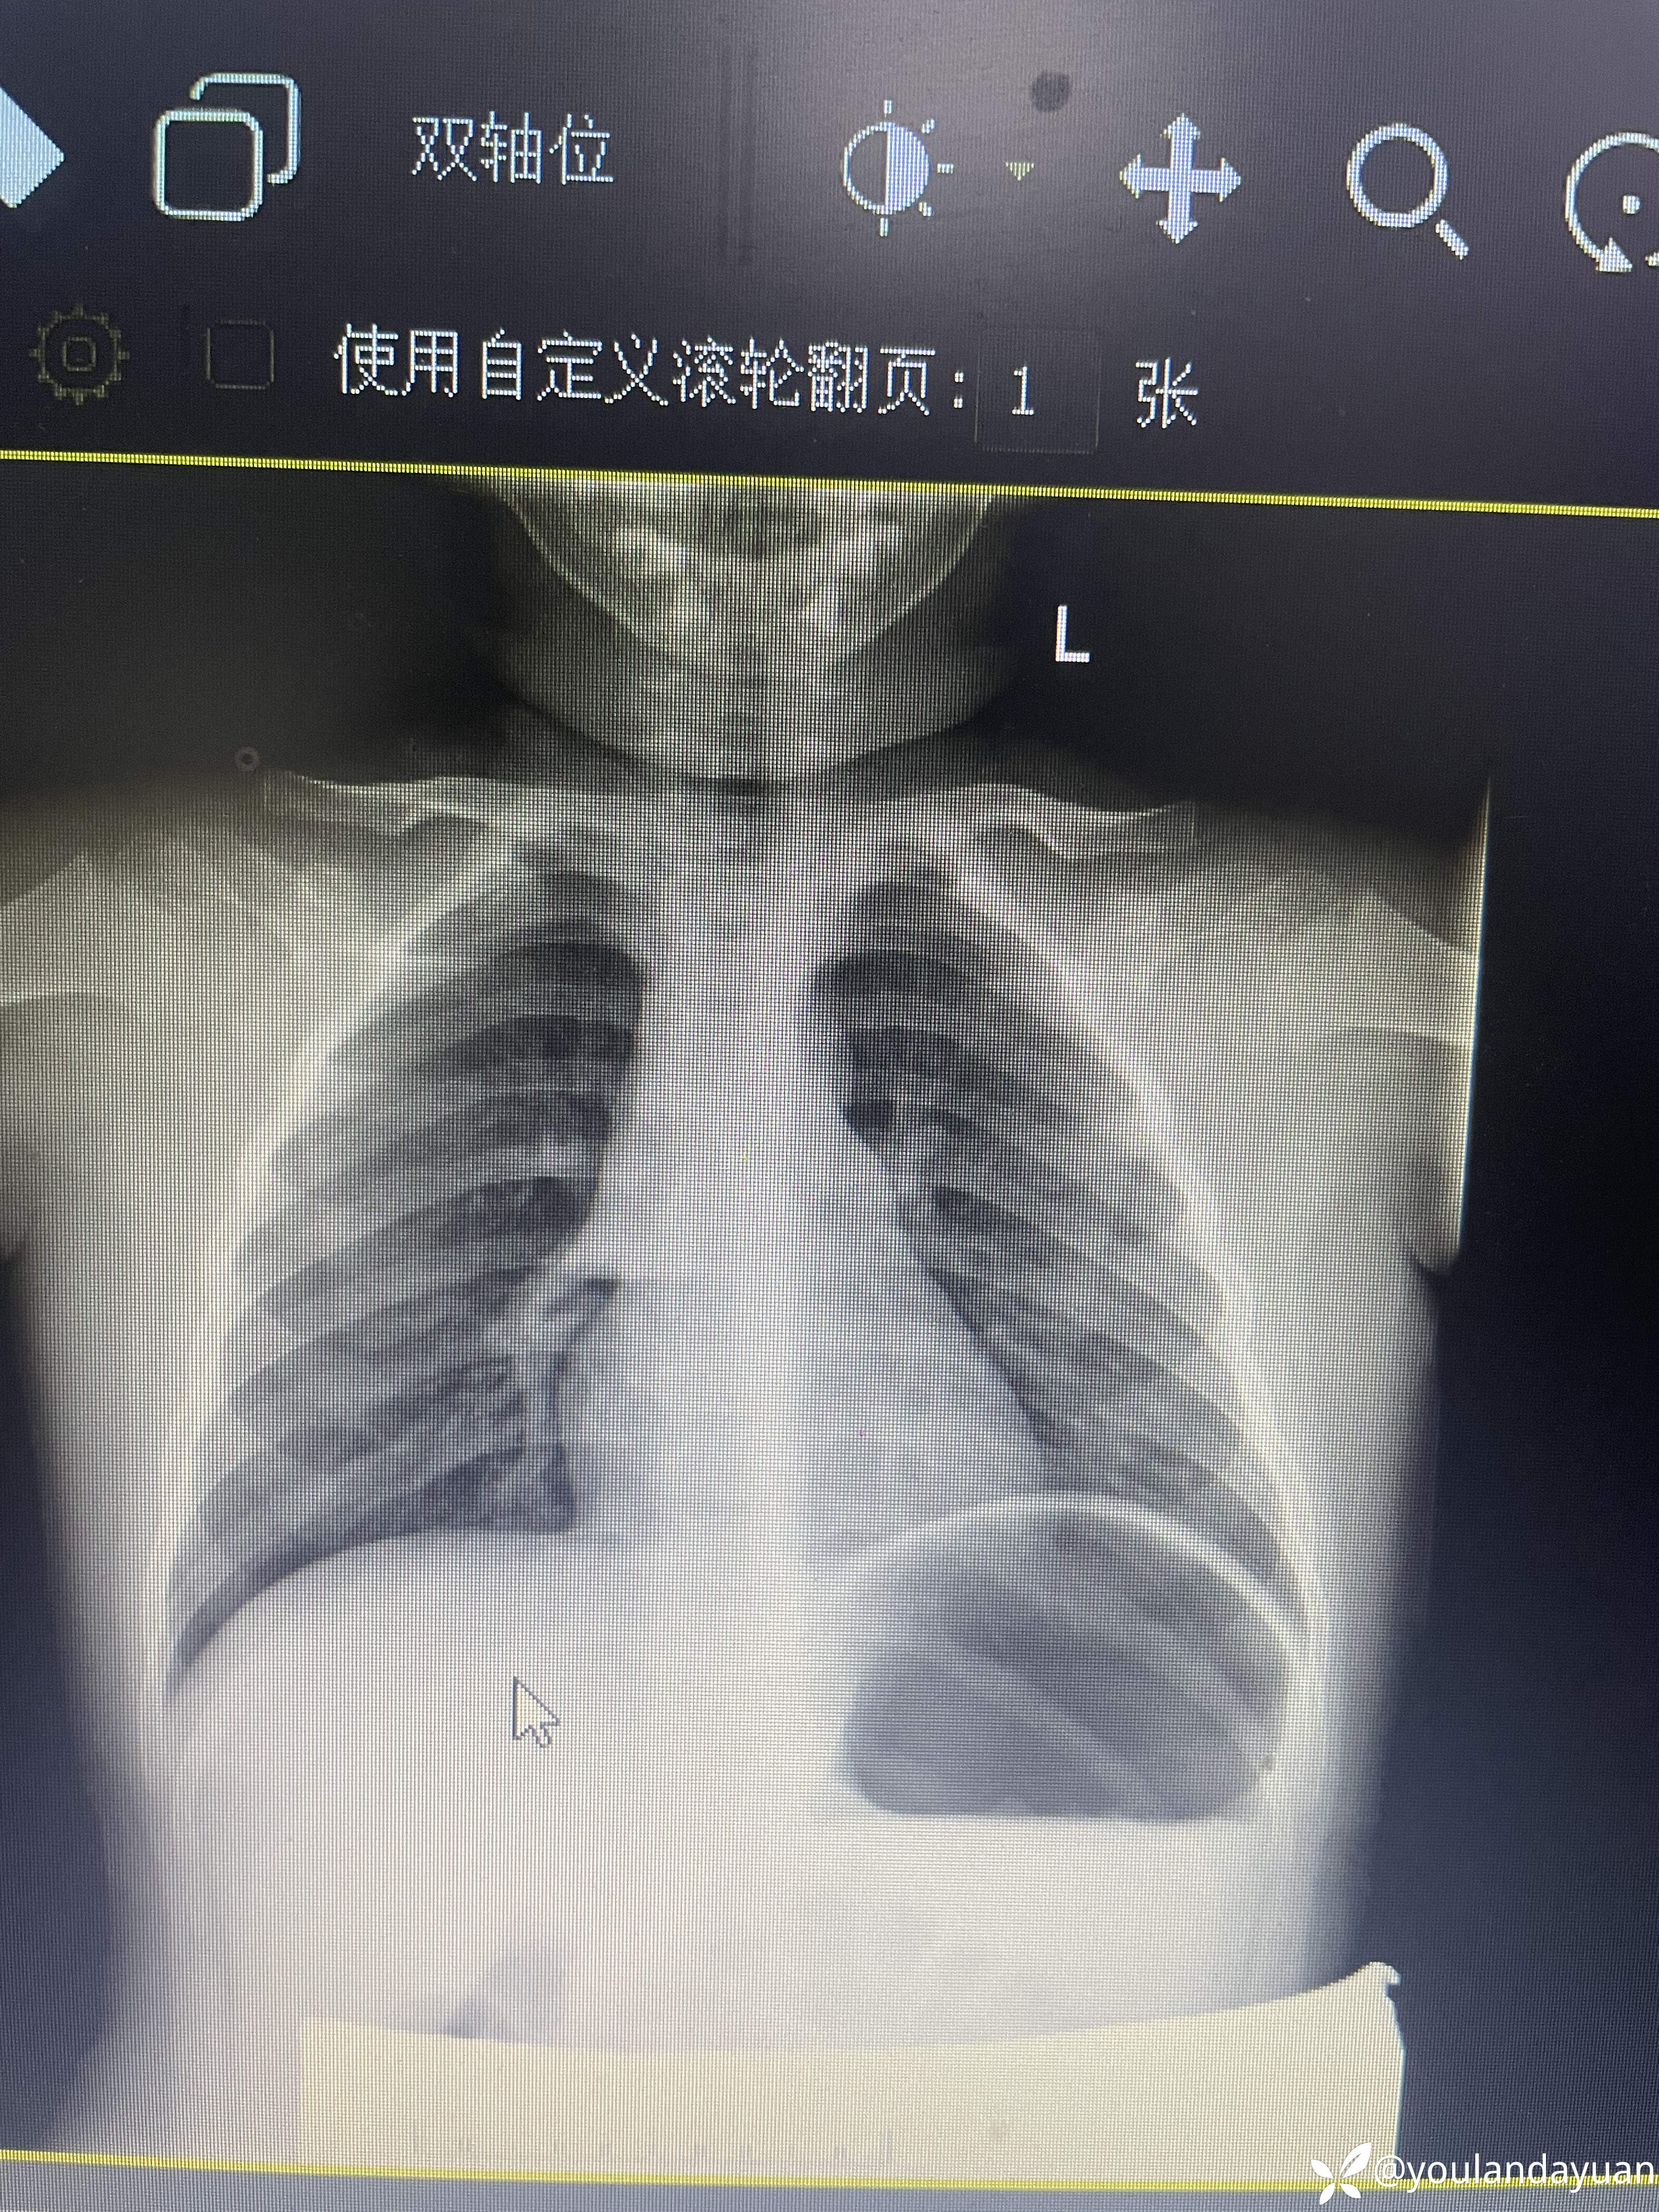

文侠 推荐患儿系50天前无明显诱因出现咳嗽,有轻度鼻炎病史,最初居家观察,20天前就诊我科,胸前提示支气管炎,肺炎支原体IGM阳性,考虑支原体感染,支气管炎,

并给予,“头孢泊肟,阿奇,氯雷他定”5天,环酯红霉素5天,咳嗽明显减轻。停药5天后出现咳血两次。

今日复查胸片

请教各位老师,考虑什么?